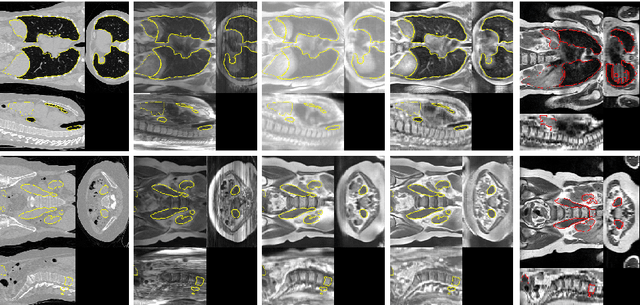

Abstract:Deformable Image Registration (DIR) of MR and CT images is one of the most challenging registration task, due to the inherent structural differences of the modalities and the missing dense ground truth. Recently cycle Generative Adversarial Networks (cycle-GANs) have been used to learn the intensity relationship between these 2 modalities for unpaired brain data. Yet its usefulness for DIR was not assessed. In this study we evaluate the DIR performance for thoracic and abdominal organs after synthesis by cycle-GAN. We show that geometric changes, which differentiate the two populations (e.g. inhale vs. exhale), are readily synthesized as well. This causes substantial problems for any application which relies on spatial correspondences being preserved between the real and the synthesized image (e.g. plan, segmentation, landmark propagation). To alleviate this problem, we investigated reducing the spatial information provided to the discriminator by decreasing the size of its receptive fields. Image synthesis was learned from 17 unpaired subjects per modality. Registration performance was evaluated with respect to manual segmentations of 11 structures for 3 subjects from the VISERAL challenge. State-of-the-art DIR methods based on Normalized Mutual Information (NMI), Modality Independent Neighborhood Descriptor (MIND) and their novel combination achieved a mean segmentation overlap ratio of 76.7, 67.7, 76.9%, respectively. This dropped to 69.1% or less when registering images synthesized by cycle-GAN based on local correlation, due to the poor performance on the thoracic region, where large lung volume changes were synthesized. Performance for the abdominal region was similar to that of CT-MRI NMI registration (77.4 vs. 78.8%) when using 3D synthesizing MRIs (12 slices) and medium sized receptive fields for the discriminator.